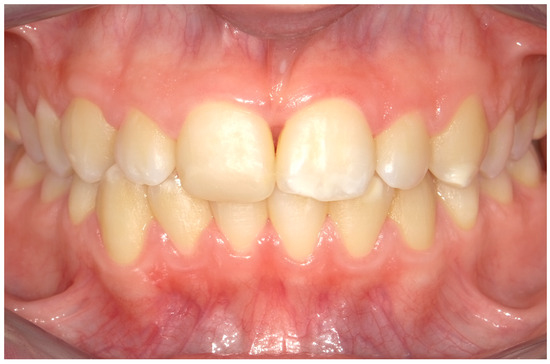

4.1. Case 1

4.2. Case 2